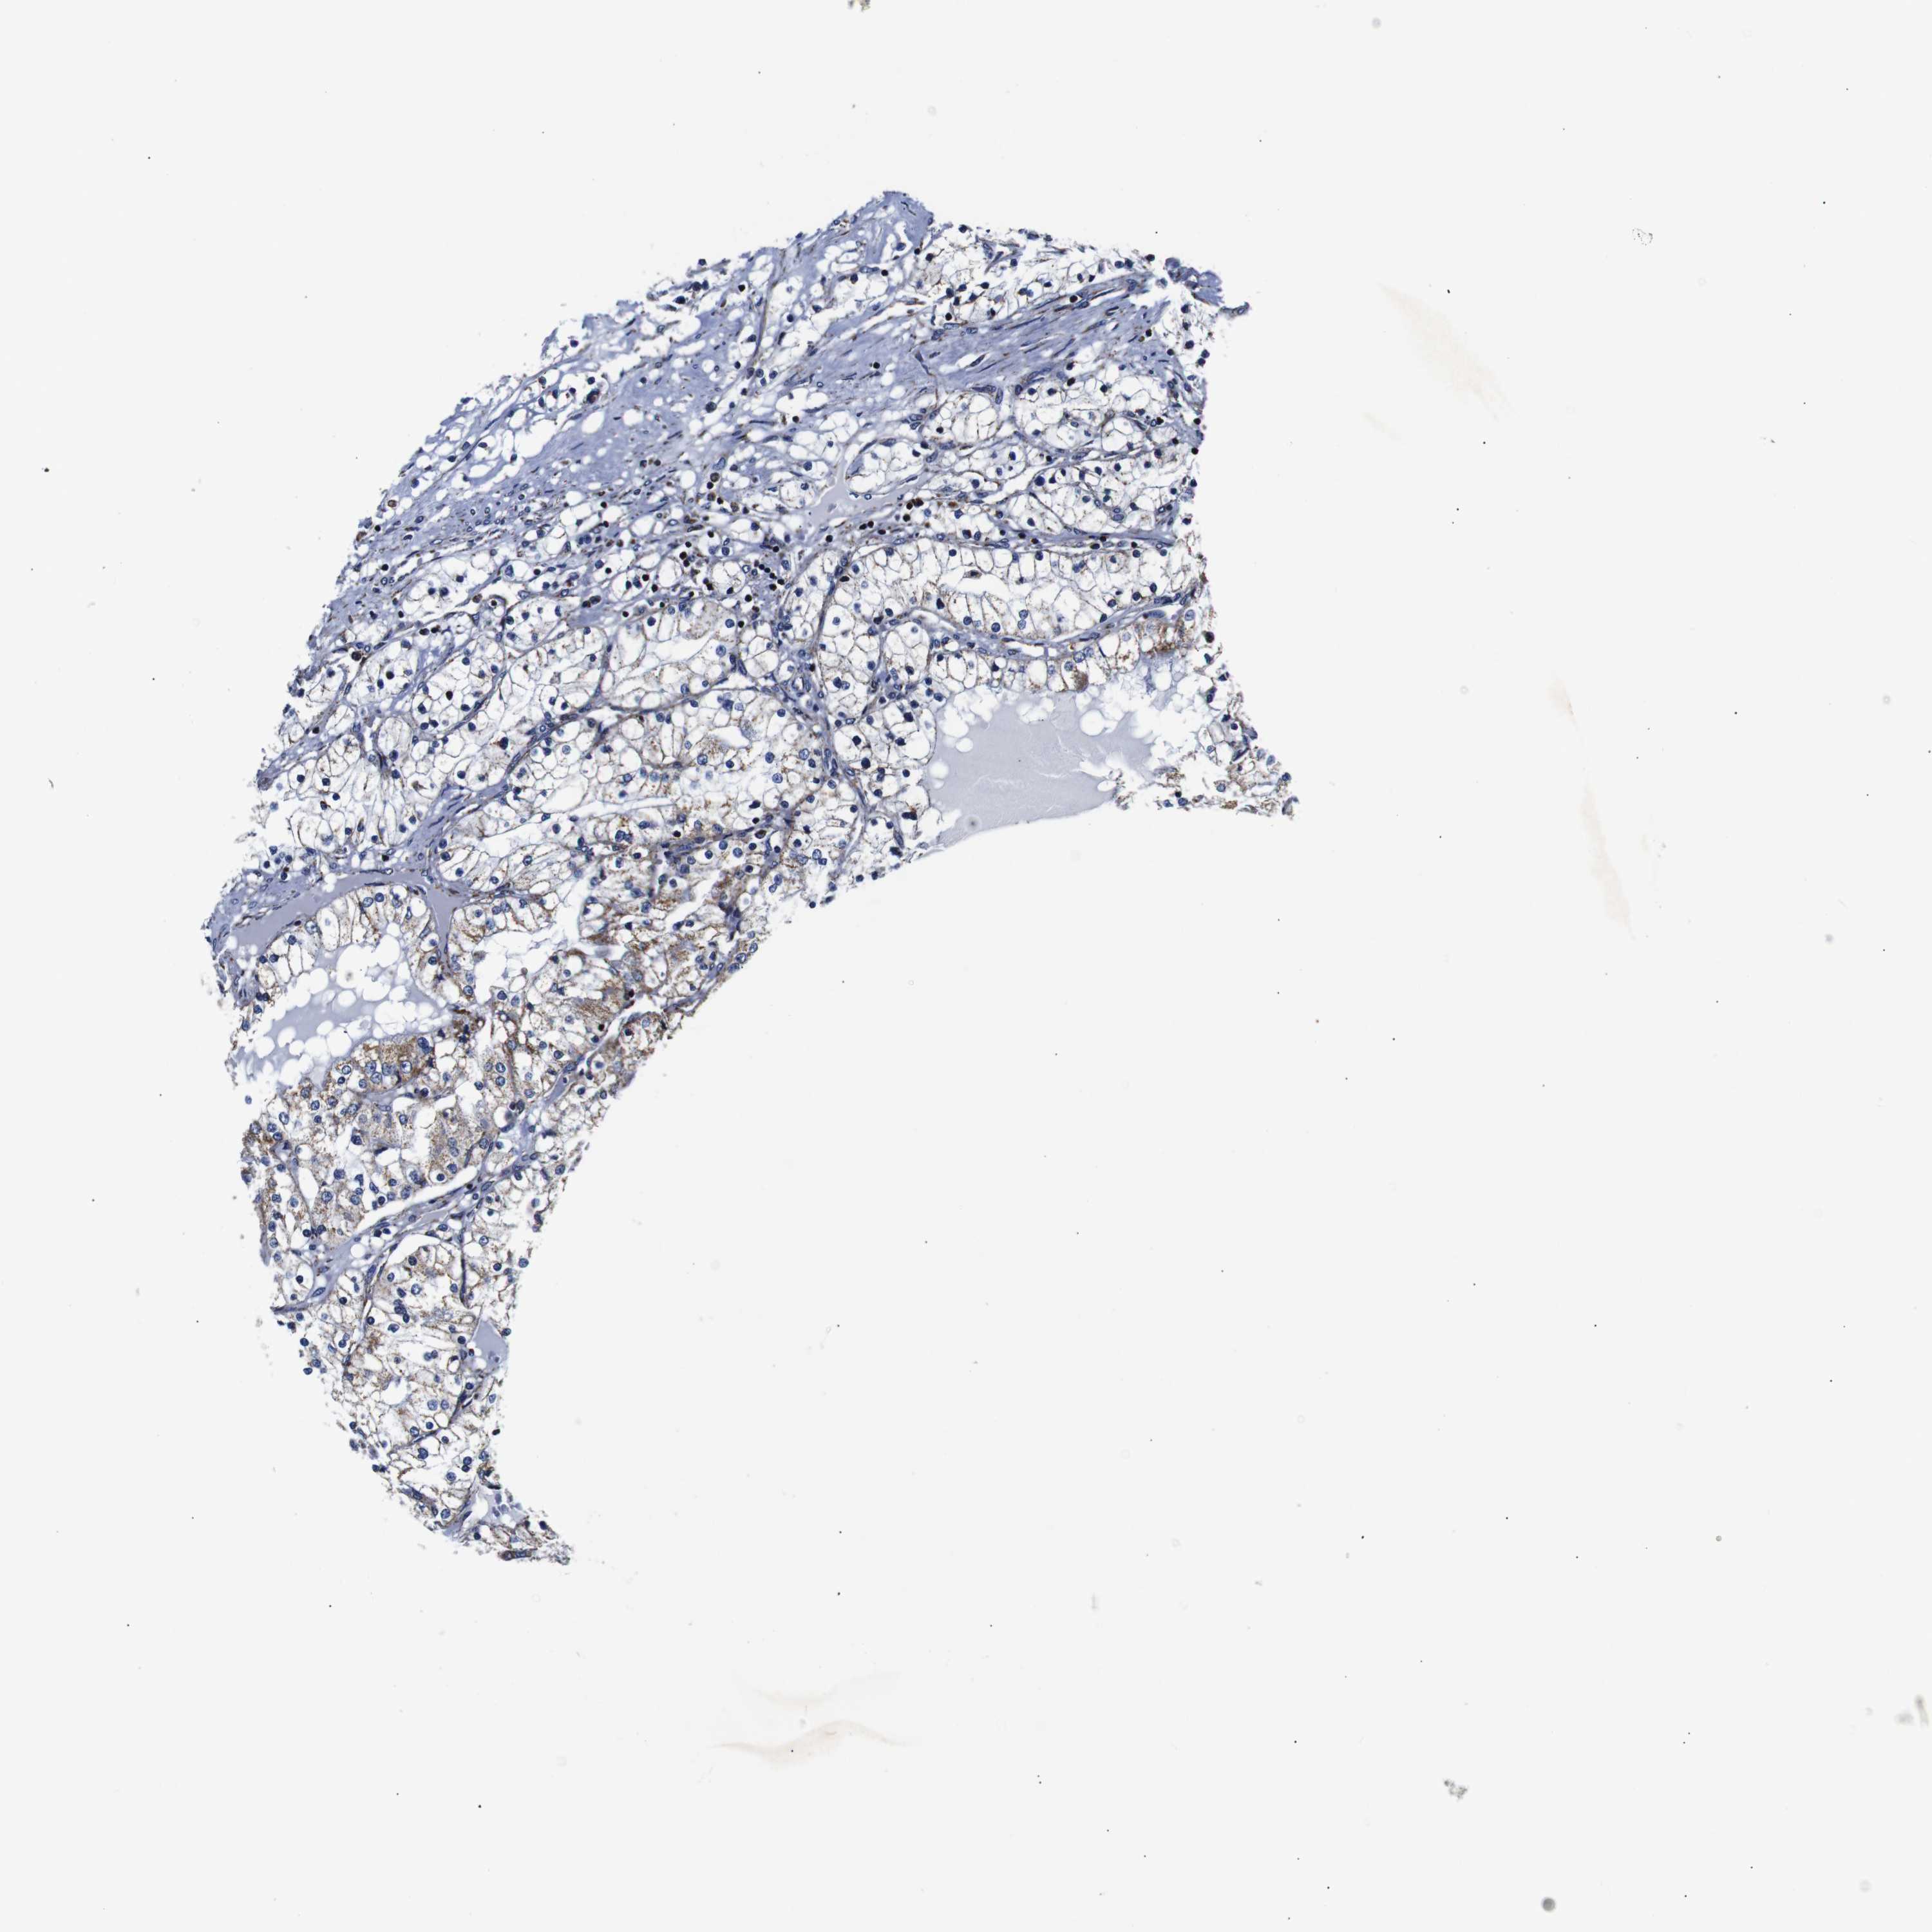

KIDNEY RENAL CLEAR CELL CARCINOMA (VALIDATION) - Interactive survival scatter ploti

The Survival Scatter plot shows the clinical status (i.e. dead or alive) for all individuals in the patient cohort, based on the same data that underlies the corresponding Kaplan-Meier plots. Patients that are alive at last time for follow-up are shown in blue and patients who have died during the study are shown in red.

The x-axis shows the expression levels (FPKM) of the investigated gene in the tumor tissue at the time of diagnosis. The y-axis shows the follow-up time after diagnosis (years). Both axes are complimented with kernel density curves demonstrating the data density over the axes. The top density plot shows the expression levels (FPKM) distribution among dead (red) and alive patients (blue). The right density plot shows the data density of the survived years of dead patients with high and low expression levels respectively, stratified using the cutoff indicated by the vertical dashed line through the Survival Scatter plot. This cutoff is automatically defined based on the FPKM cutoff that minimizes the p-score. The cutoff can be changed by dragging the vertical line or by entering a cutoff value in the square labeled "Current cut-off".

Under the Survival Scatter plot the p-score landscape (black curve; left axis) is shown together with dead median separation (red curve; right axis). Dead median separation is the difference in median mRNA expression between patients who have died with high and low expression, respectively. It is calculated as follows: median FPKM expression of dead patients with high expression - median FPKM expression of dead patients with low expression. This is intended to aid the user in visually exploring custom cutoffs and the associated p-scores and dead median separation.

Individual patient data is displayed and can be filtered by clicking on one or more of the category buttons on the top of the page. Categories describing expression level and patient information include: high, low, alive, dead, female, male and tumor stages. The scale of the x-axis can be toggled between linear and log-scale by clicking on the "x log" button. Mouse-over function shows TCGA ID, patient information and mRNA expression (FPKM) for each patient.

& Survival analysisi

Kaplan-Meier plots summarize results from analysis of correlation between mRNA expression level and patient survival. Patients were divided based on level of expression into one of the two groups "low" (under cut off) or "high" (over cut off). X-axis shows time for survival (years) and y-axis shows the probability of survival, where 1.0 corresponds to 100 percent.

FKBP9 is not prognostic in Kidney Renal Clear Cell Carcinoma (validation)

Best expression cut offi

Based on the FPKM value of each gene, patients were classified into two groups and association between prognosis (survival) and gene expression (FPKM) was examined. The best expression cut-off refers the FPKM value that yields maximal difference with regard to survival between the two groups at the lowest log-rank P-value. Best expression cut-off was selected based on survival analysis .

When clicking on this number, the vertical dashed line indicating cut-off, the interactive survival plot, and the Kaplan-Meier curve will be adjusted to show results based on the best expression cut-off.

: 108.3

P scorei

Log-rank P value for Kaplan-Meier plot showing results from analysis of correlation between mRNA expression level and patient survival.

N/A

TCGA RNA samplesi

RNA-seq data is reported as average FPKM (number Fragments Per Kilobase of exon per Million reads), generated by the The Cancer Genome Atlas (TCGA) .

Normal distribution across the dataset is visualized with box plots, shown as median and 25th and 75th percentiles. Points are displayed as outliers if they are above or below 1.5 times the interquartile range. FPKM values of the individual samples are presented next to the box plot.

Average pTPM 86.9

Number of samples 100